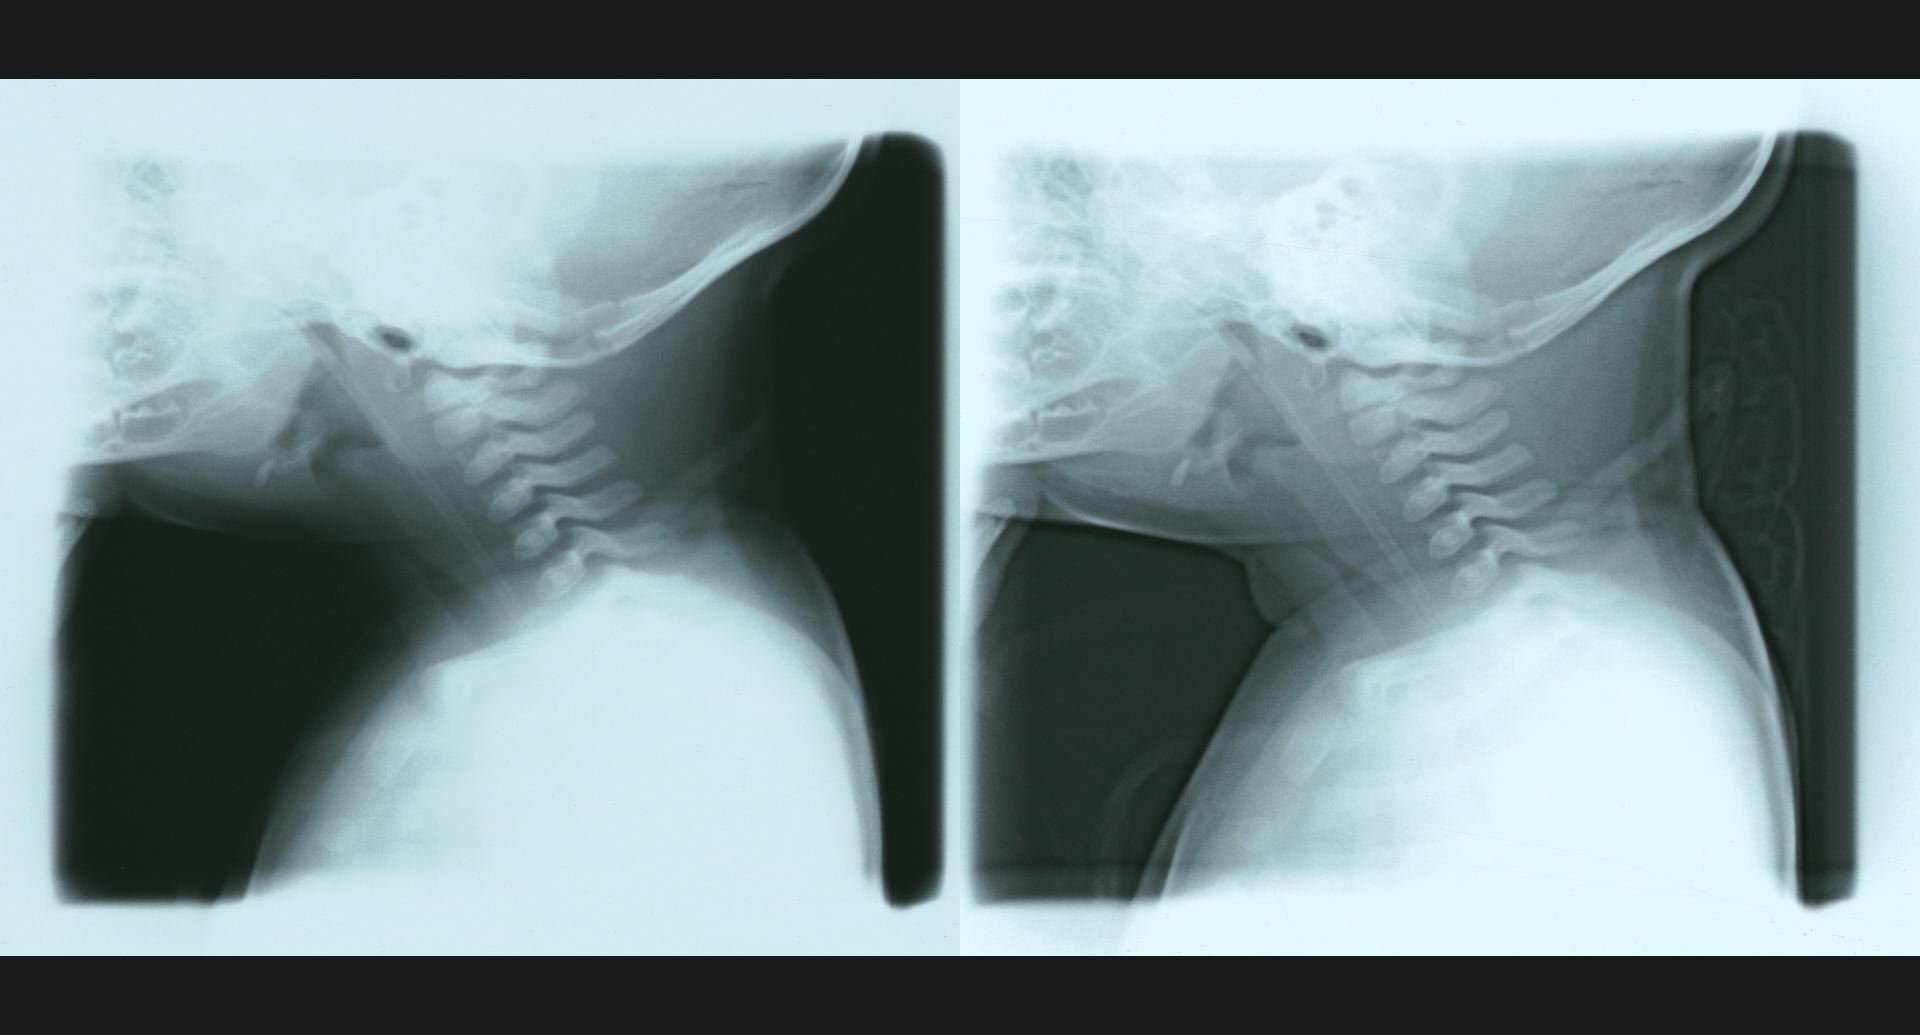

fig.4(104KB) :新生児の気管狭窄